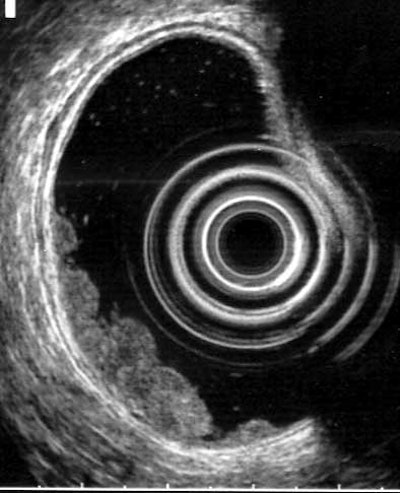

His father's surgery went smoothly, Pickhardt told AuntMinnie.com the next day. And the patient, an otherwise-healthy 65-year-old, was kind enough to allow images of the 5-cm lobulated rectal "carpet" lesion to be included in this article.

| In an asymptomatic 65-year-old male patient, 3D endoluminal view in virtual colonoscopy shows lobulated "carpet" lesion in rectum (arrowheads, above). The top arrow indicates the rectal catheter. Same-day conventional colonoscopy shows the endoscopic view of the same lesion (below). Same-day endorectal ultrasound (as part of conventional colonoscopy) shows a broad superficial lesion along the rectal wall with no evidence of bowel-wall invasion (bottom). The biopsy showed villous adenoma with high-grade dysplasia; histological results are pending. All images courtesy of Dr. Perry Pickhardt. |